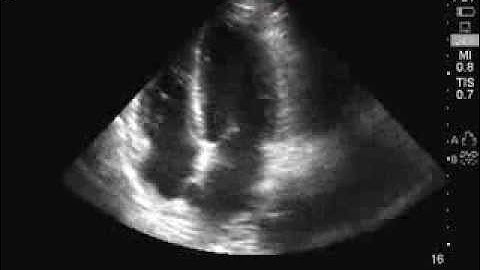

Apical 4 Chamber normal